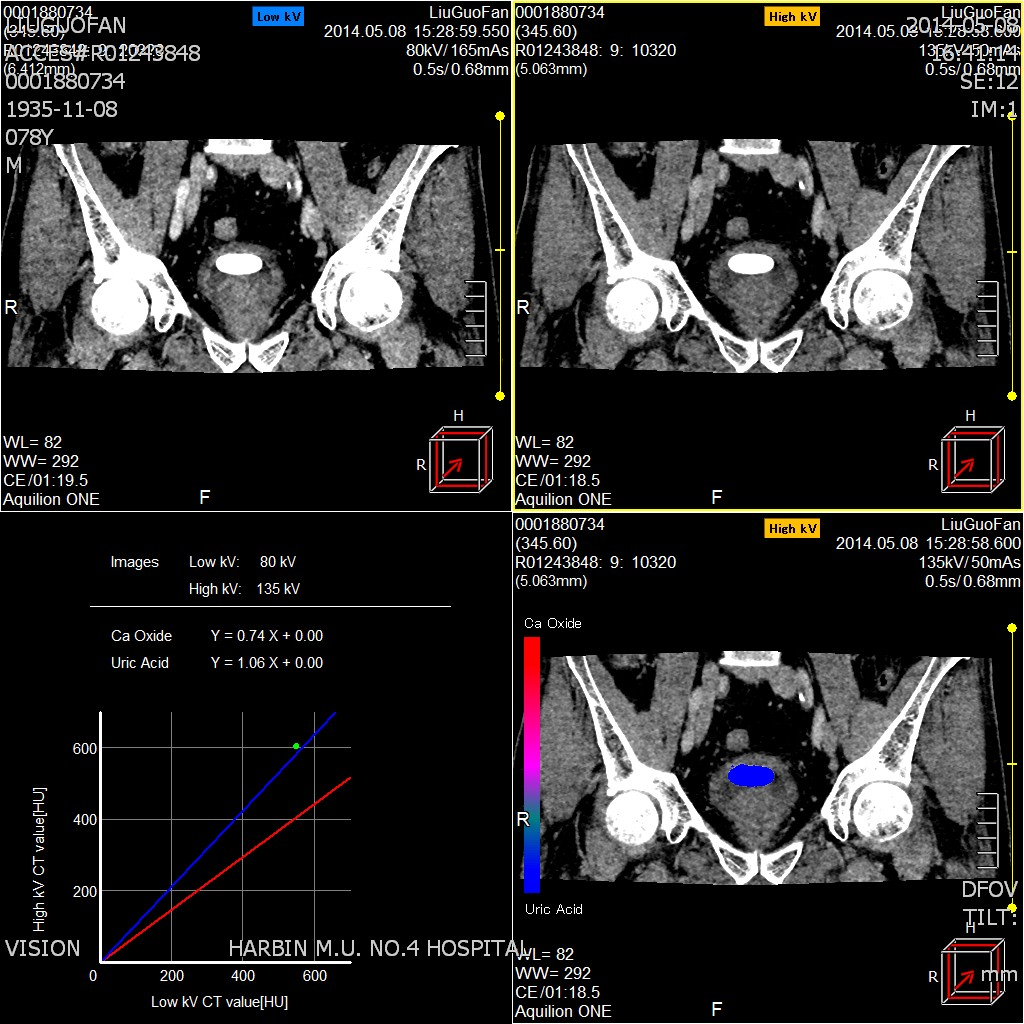

一、能谱结石分析

行体内泌尿系结石成分分析,缩小尿结石的代谢评估范围,避免患者进行不必要的检查甚至有创治疗,评估治疗效果以及判断预后 。如尿酸结石适用于非手术治疗; 磷酸铵镁结石适用于体外冲击波碎石; 草酸钙结石适用于经皮肾镜取石术治疗等 。

二、能谱痛风分析

用于痛风病的早期发现和诊断,能够明确显示尿酸盐结晶或结石 ,可以发现刚刚形成的尿酸盐结晶微粒,得到尿酸盐结晶数量、大小、位置等全面信息 ,显示尿酸盐结晶、结石对周围关节、软组织有无影响,有无骨质破坏。